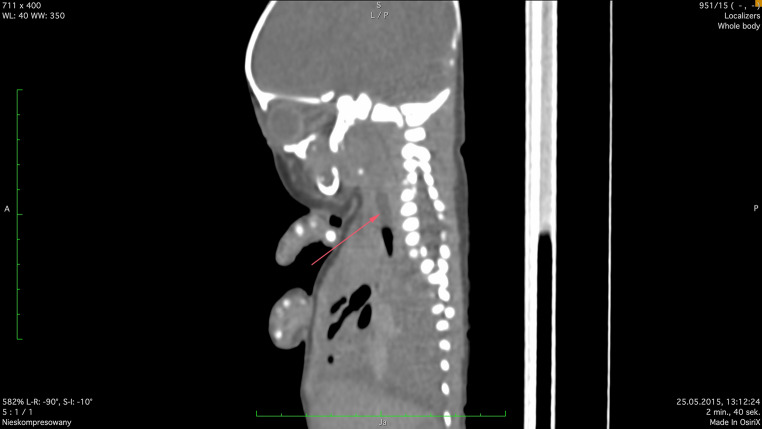

Congenital diaphragmatic hernia is associated with high risk of neonatal death. It is observed in about 1 in 3,000 live births. Fetoscopic tracheal occlusion procedure is a therapeutic option with survival rate 46.4%. Our aim was analysis of the suitability of postmortem computed tomography in the case of neonatal death occurred after fetoscopic endotracheal occlusion performed due to the severe isolated left-sided congenital diaphragmatic hernia. Postmortem computed tomography can be helpful in such cases because it allows for an objective assessment of whether the procedures used after the birth of the newborn enabled effective lung ventilation. Our case was the first use of postmortem computed tomography in neonatal death after fetoscopic endotracheal occlusion worldwide.

Abstract Image